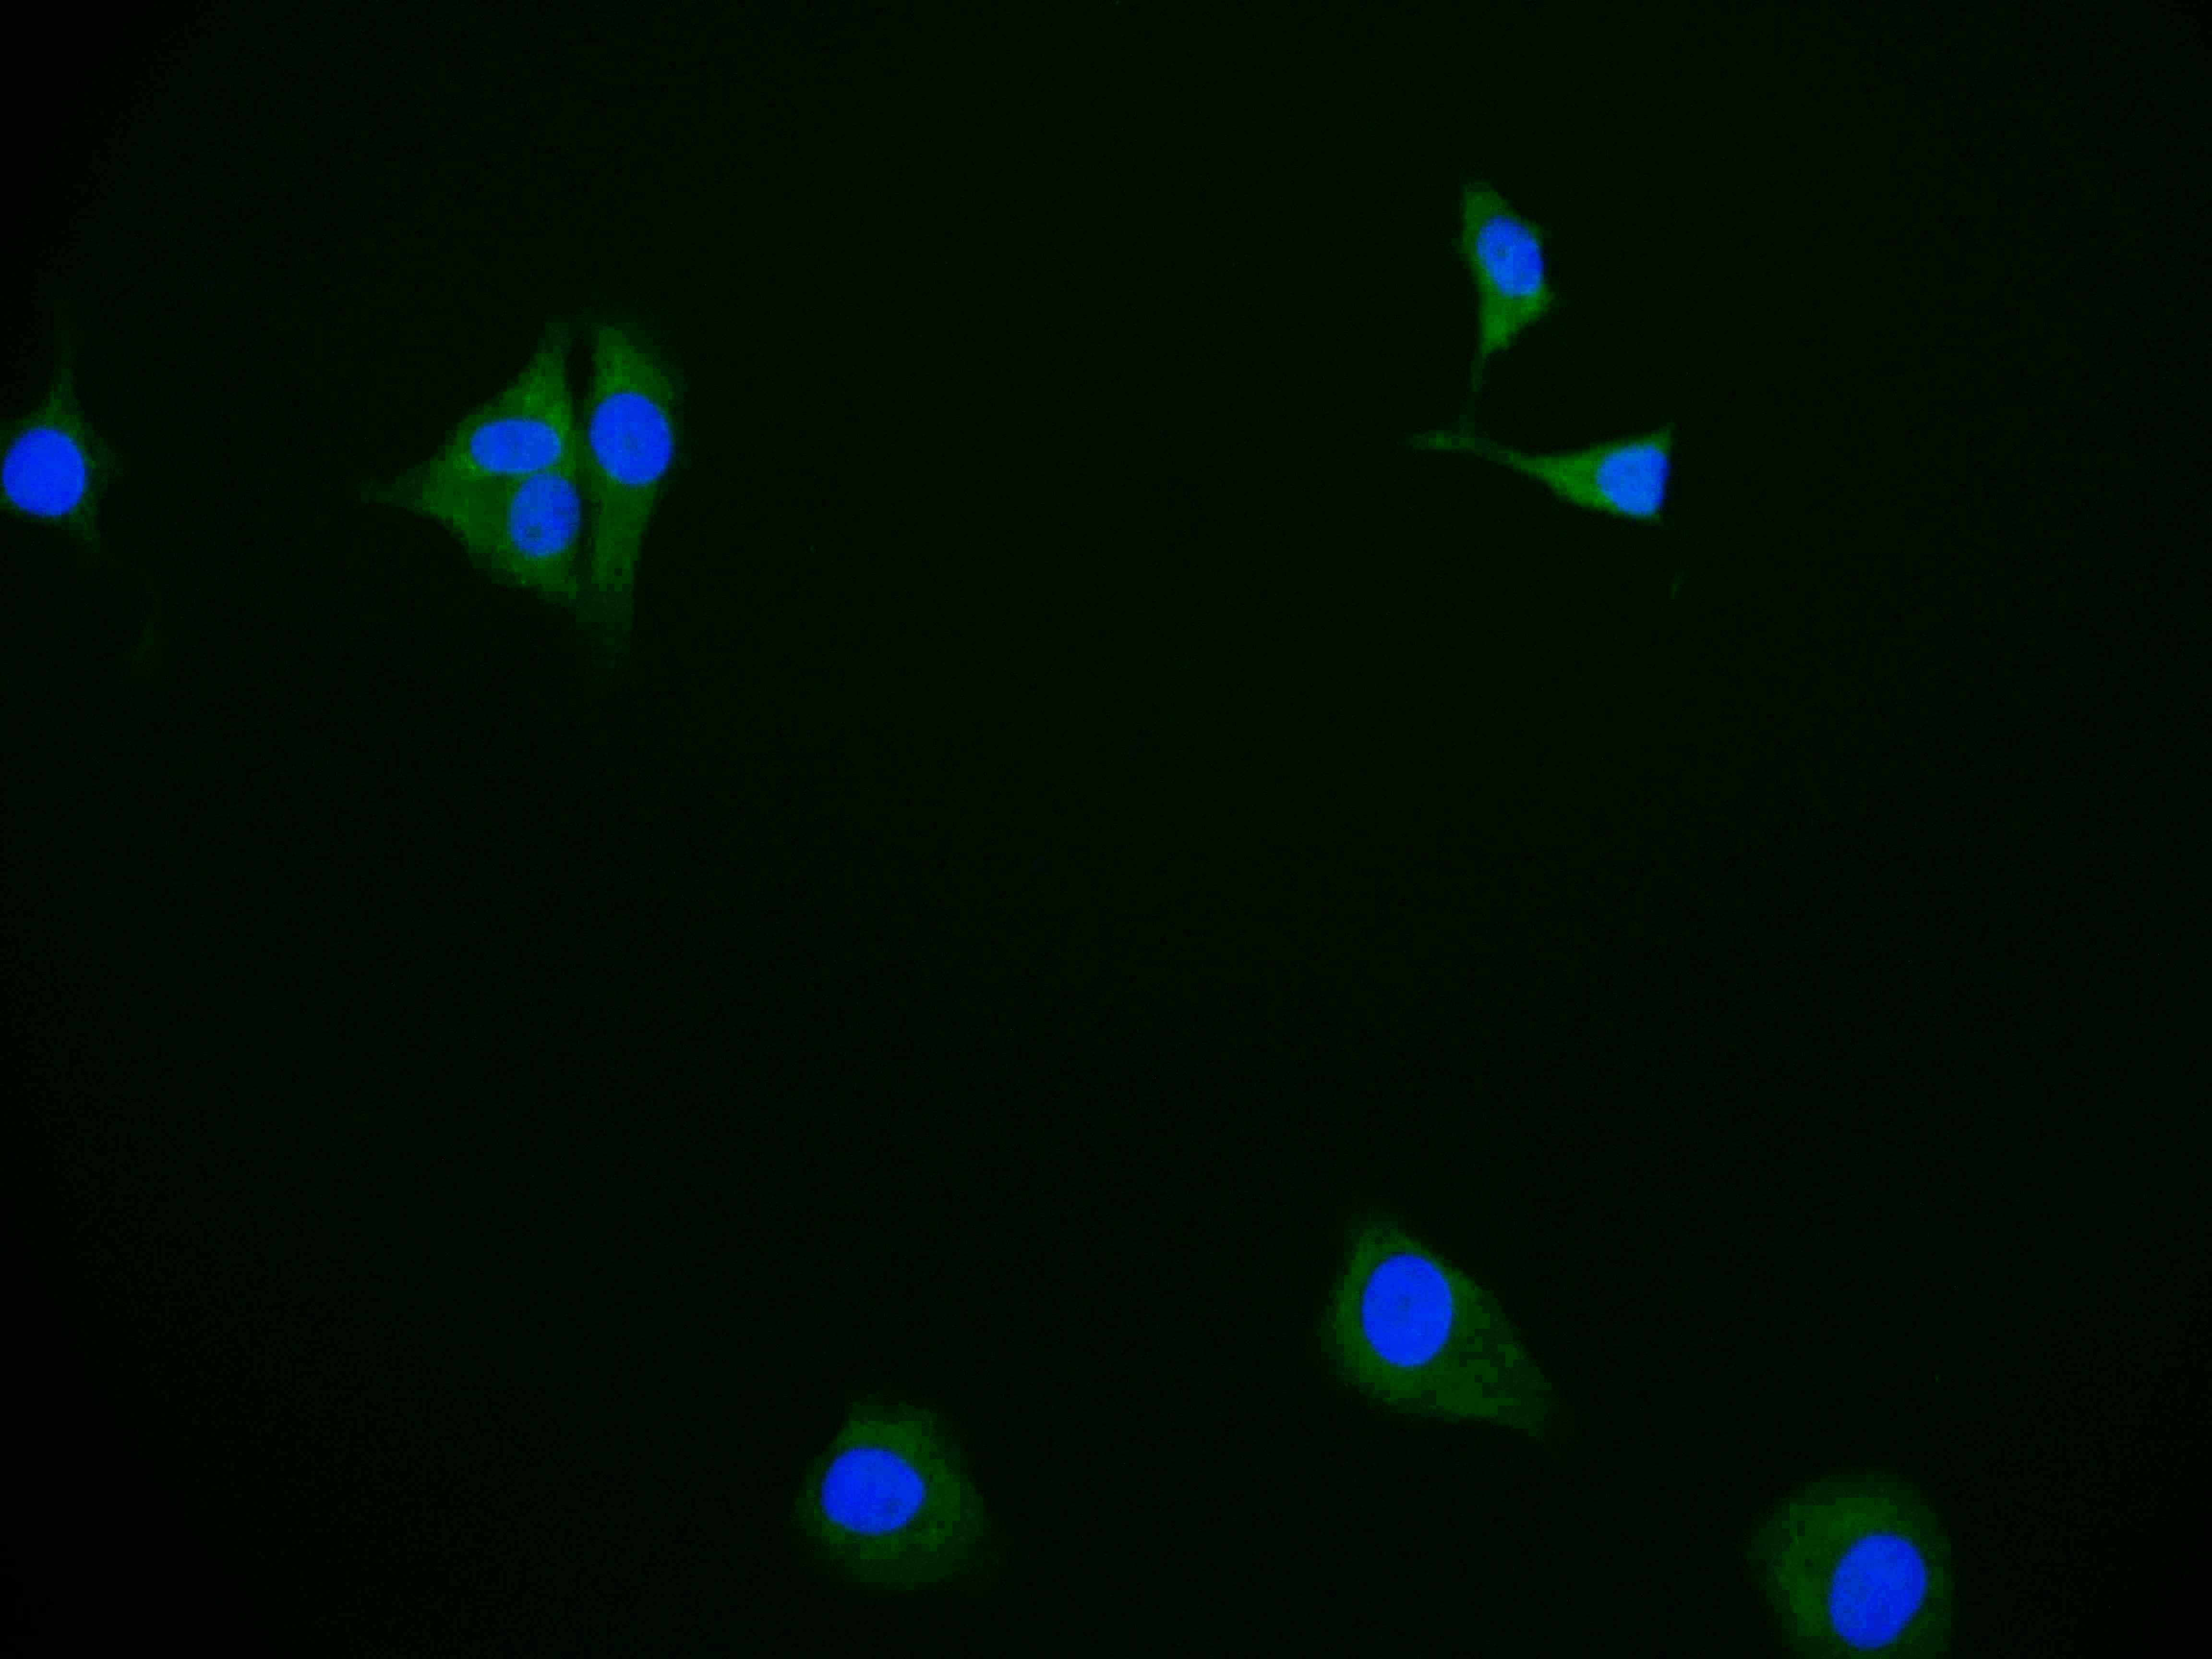

IHC image of CSB-RA983422A0HU diluted at 1:100 and staining in paraffin-embedded human adrenal gland tissue performed on a Leica BondTM system. After dewaxing and hydration, antigen retrieval was mediated by high pressure in a citrate buffer (pH 6.0). Section was blocked with 10% normal goat serum 30min at RT. Then primary antibody (1% BSA) was incubated at 4°C overnight. The primary is detected by a Goat anti-rabbit polymer IgG labeled by HRP and visualized using 0.05% DAB.

ApplicationsImmunoFluorescence, ELISA, ImmunoHistoChemistry

- ApplicationsImmunoFluorescence, ELISA, ImmunoHistoChemistry